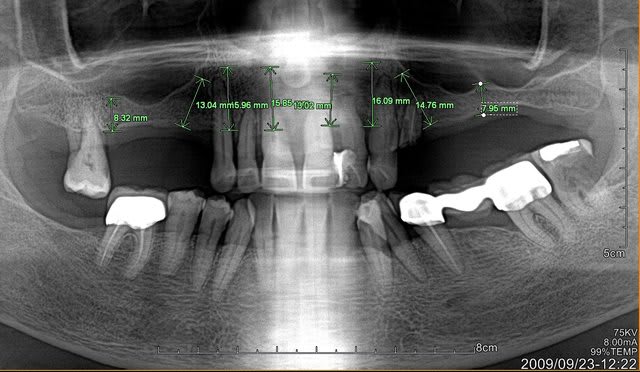

sur la deuxieme photo, j'ai notifie des longueurs approximatives pour les epaisseurs d'os disponibles.

Que pensez vous d'un all on 6 avec les 6 anterieurs ?

Ps: la patiente n'a pas forcement les moyens de faire un bridge sur 8 implants...

patiente motivée et sympa, sourire pas du tout gingival, de l'os assez bien exploitable (un peu moins du cote de 25-26, mais je vais me débrouiller soit avec implants courts 6 ou 8mm, soit avec une Summers et poser des 10mm)

Niveau nombre d'implants , je vais plutôt tabler soit sur 8 ou 9 implants et remplacer de 16 à 26.